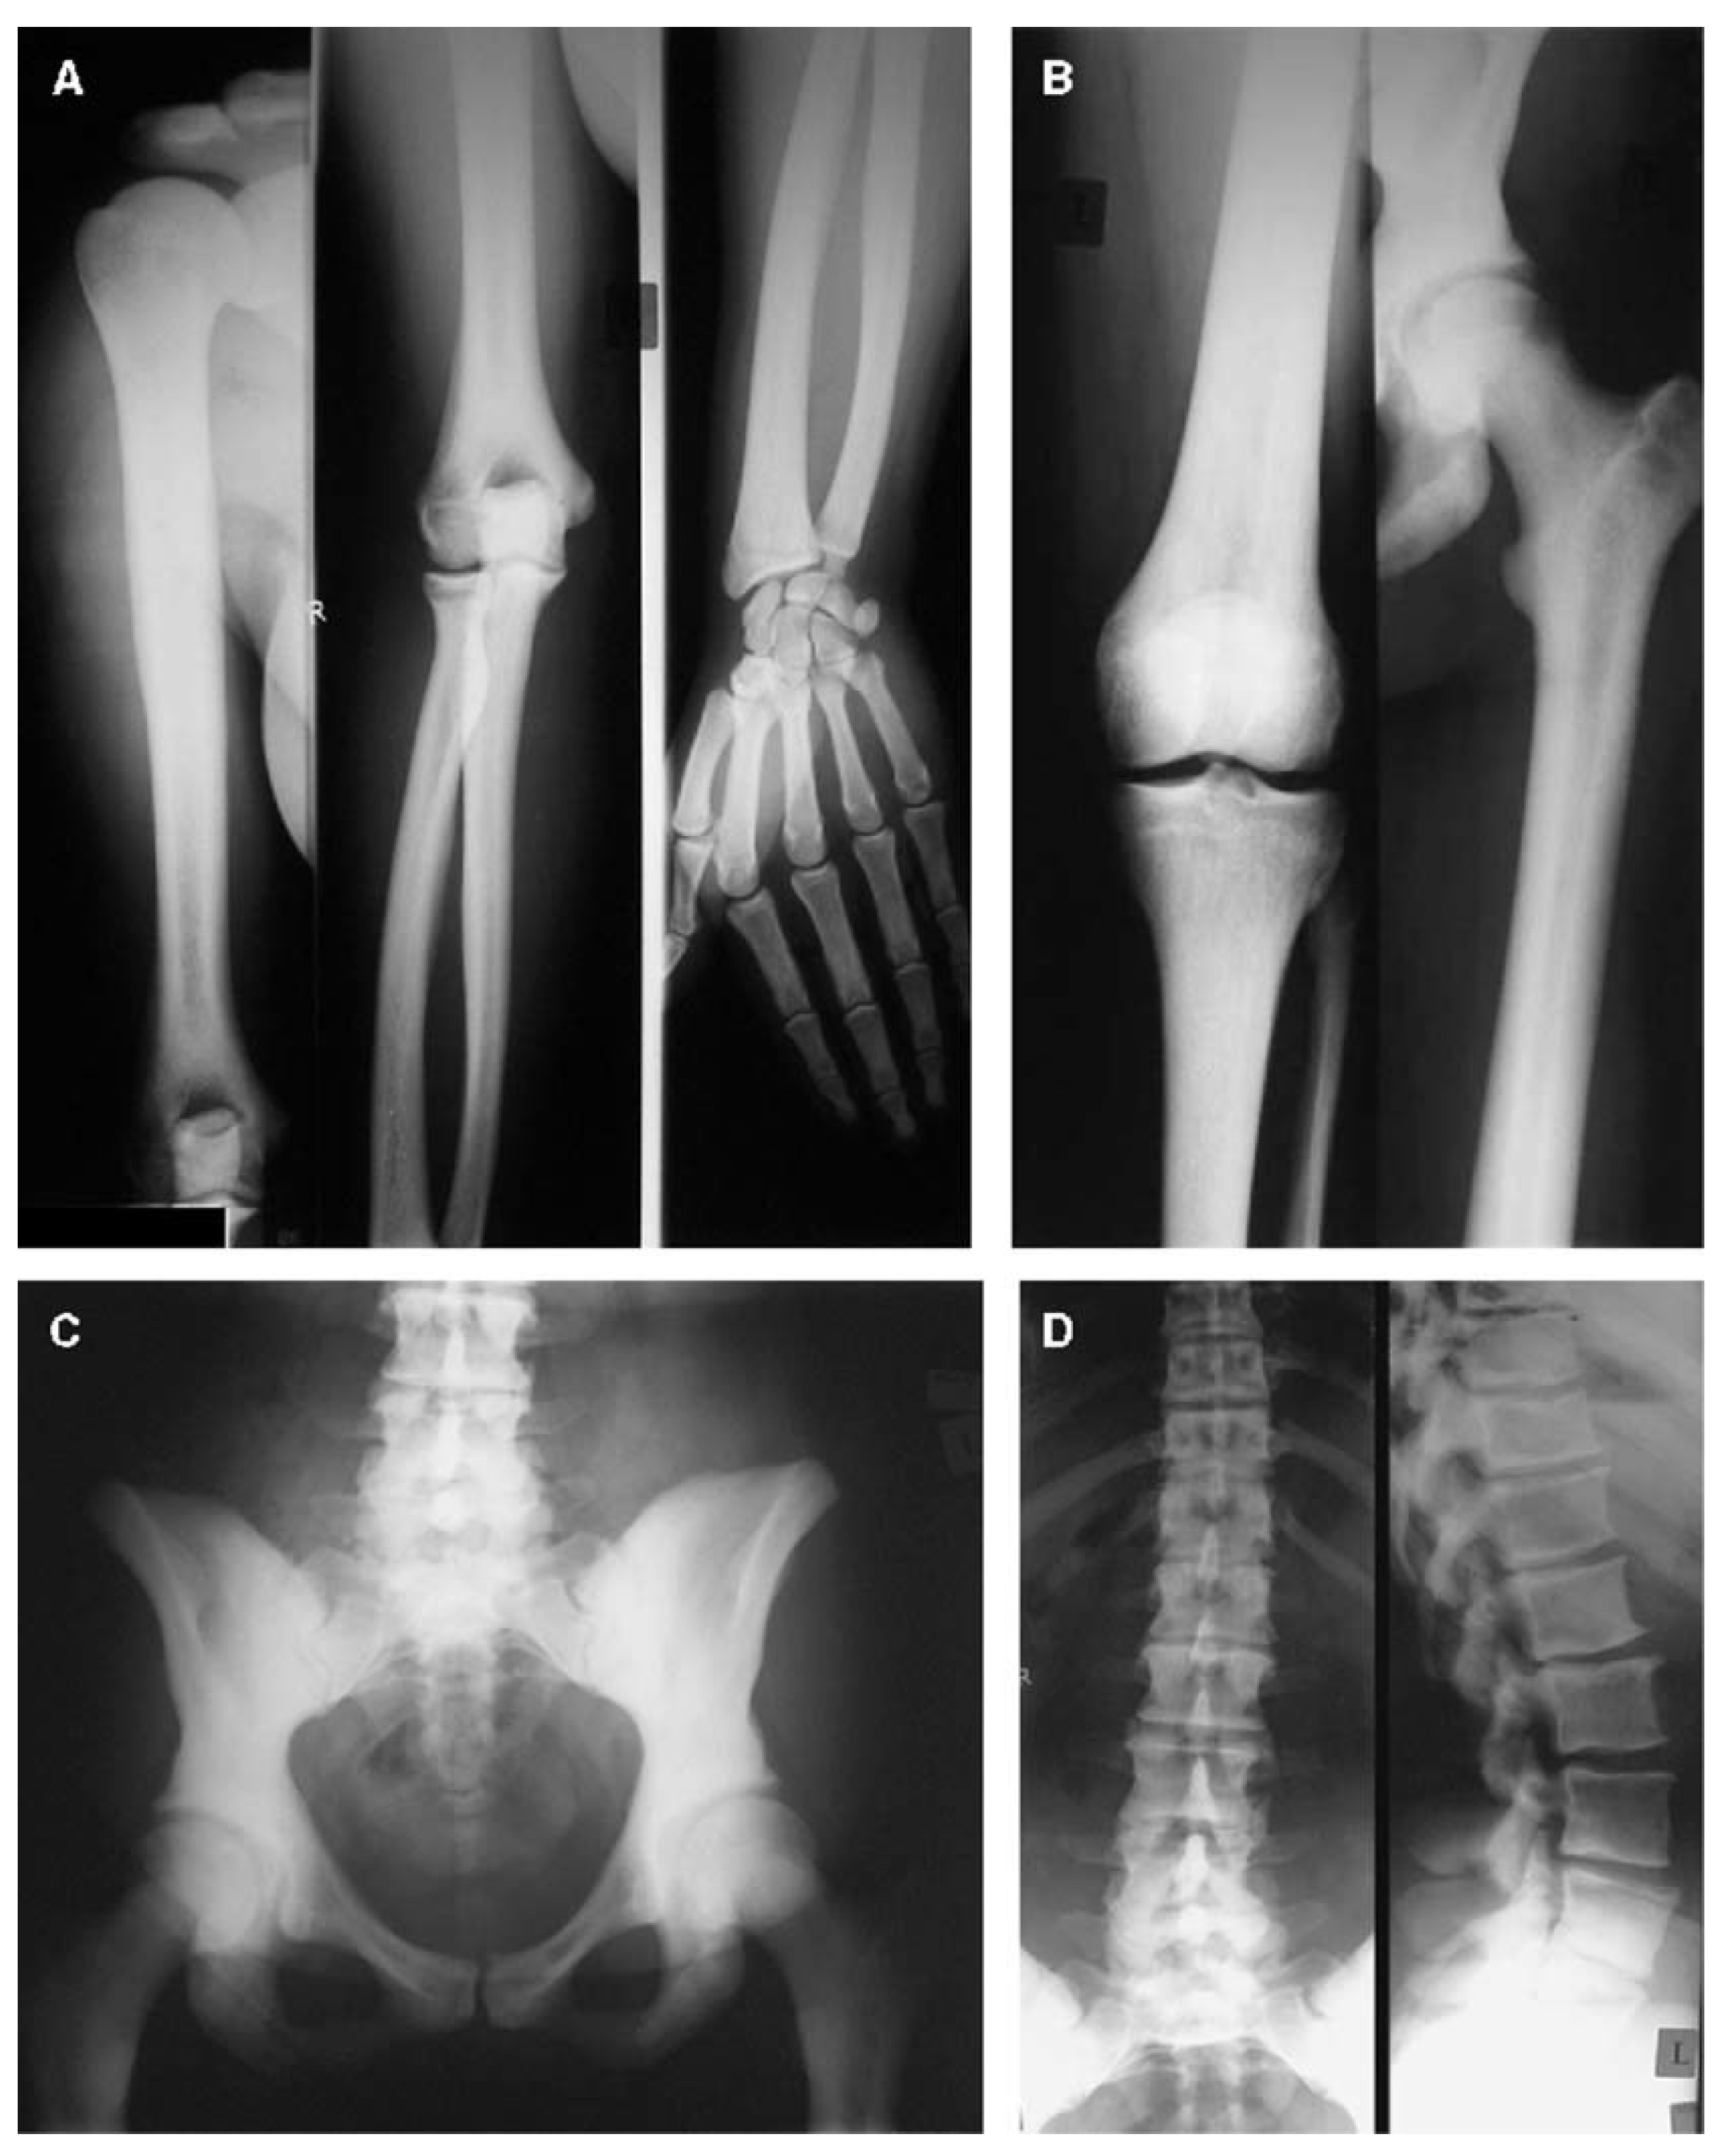

- Littman, J.; Phornphutkul, C.; Saade, C.; Katarincic, J.; Aaron, R. Osteoporosis, Fractures, and Blindness Due to a Missense Mutation in the LRP5 Receptor. Orthop. Res. Rev. 2023, 15, 39–45. [Google Scholar] [CrossRef] [PubMed]